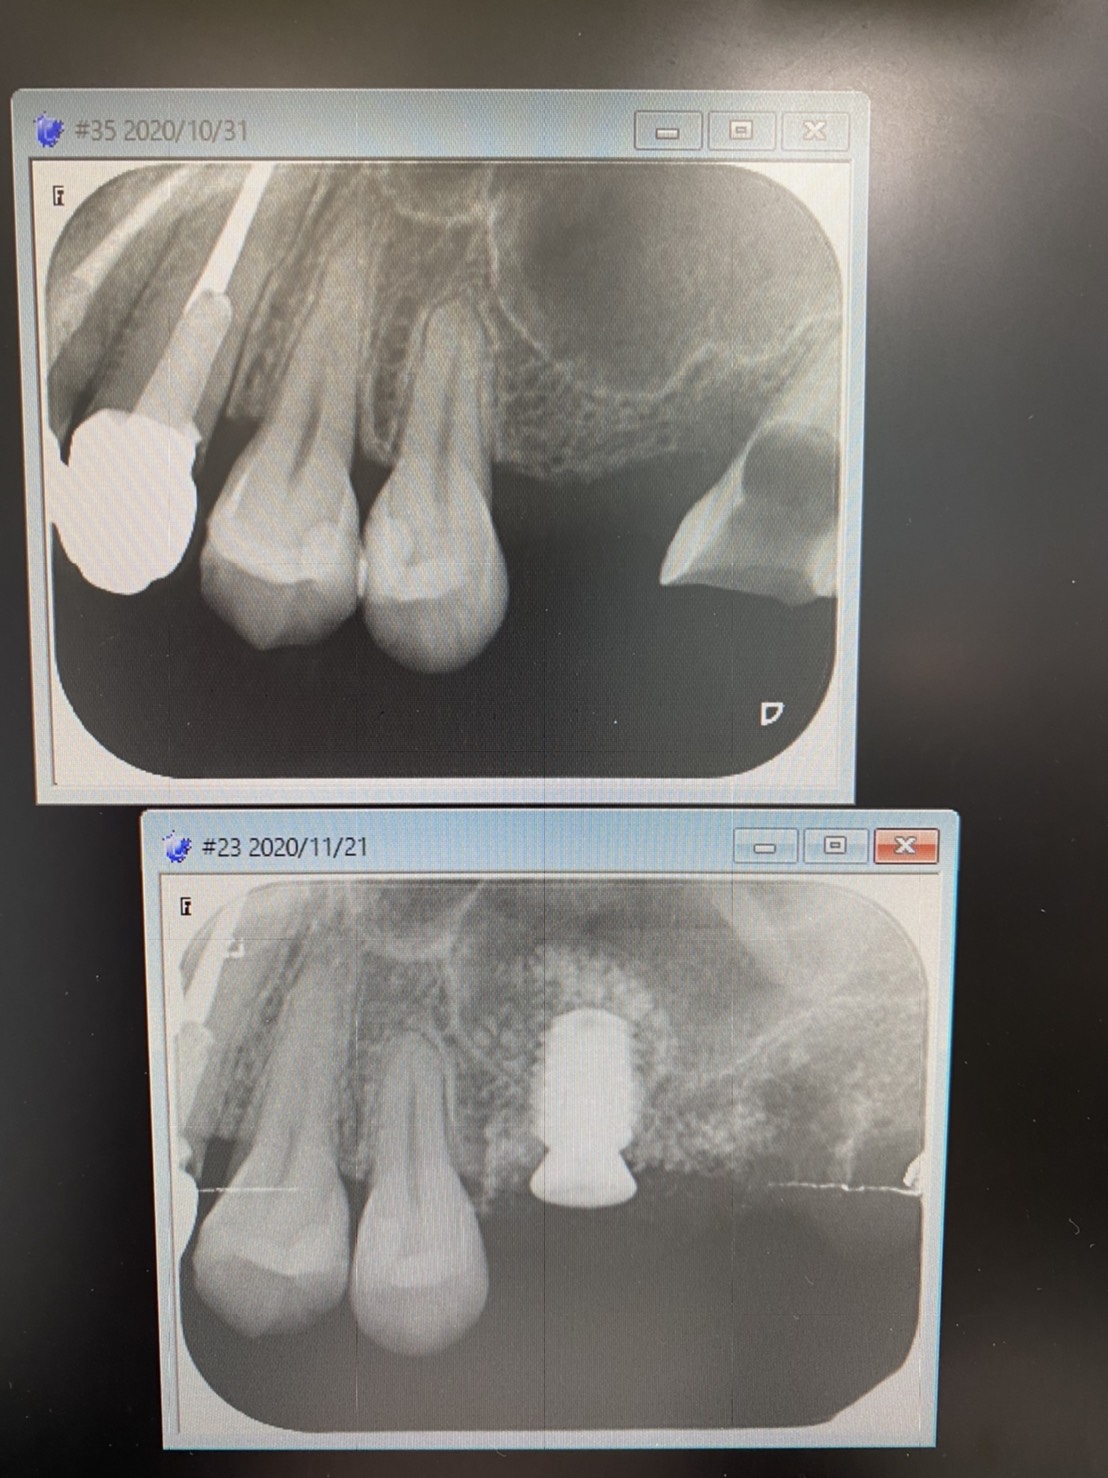

十分な挙上量も得られ、直径6長さ7ミリディープスレットインプラント体を埋入しました。

オペ後のISQ値(インプラント安定数値)も良く、2ヶ月後には仮歯を入れられる最速‼︎‼︎